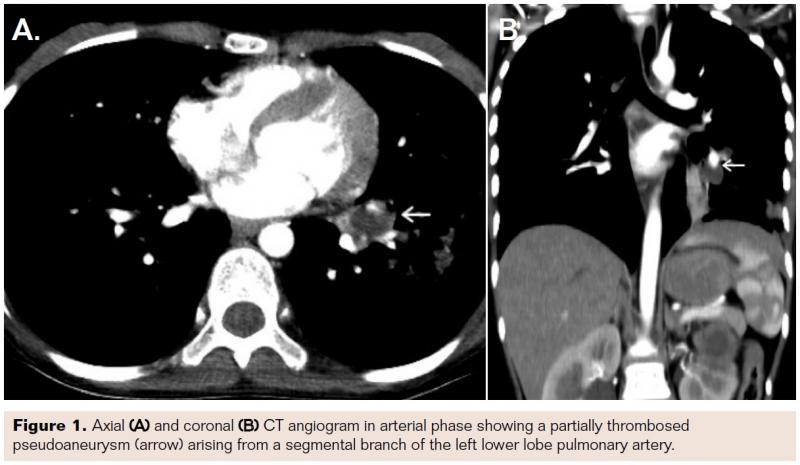

A computed tomography (CT) angiogram of the thorax was done, which showed a partially thrombosed pseudoaneurysm arising from a segmental branch of the left lower lobe pulmonary artery (Figure 1A and 1B), measuring approximately 10 mm. There were also multiple cavitating nodules in both the lungs, consistent with the past history of fungal pneumonia. A diagnosis of postinfectious mycotic pseudoaneurysm of the pulmonary artery was made and a catheter angiogram was planned with intent of endovascular intervention.